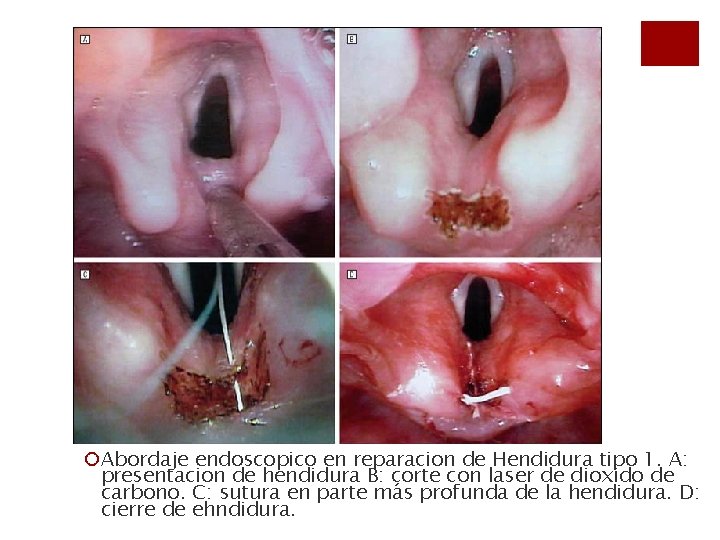

¡Abordaje endoscopico en reparacion de Hendidura tipo 1. A: presentacion de hendidura B: corte con laser de dioxido de carbono. C: sutura en parte más profunda de la hendidura. D: cierre de ehndidura.